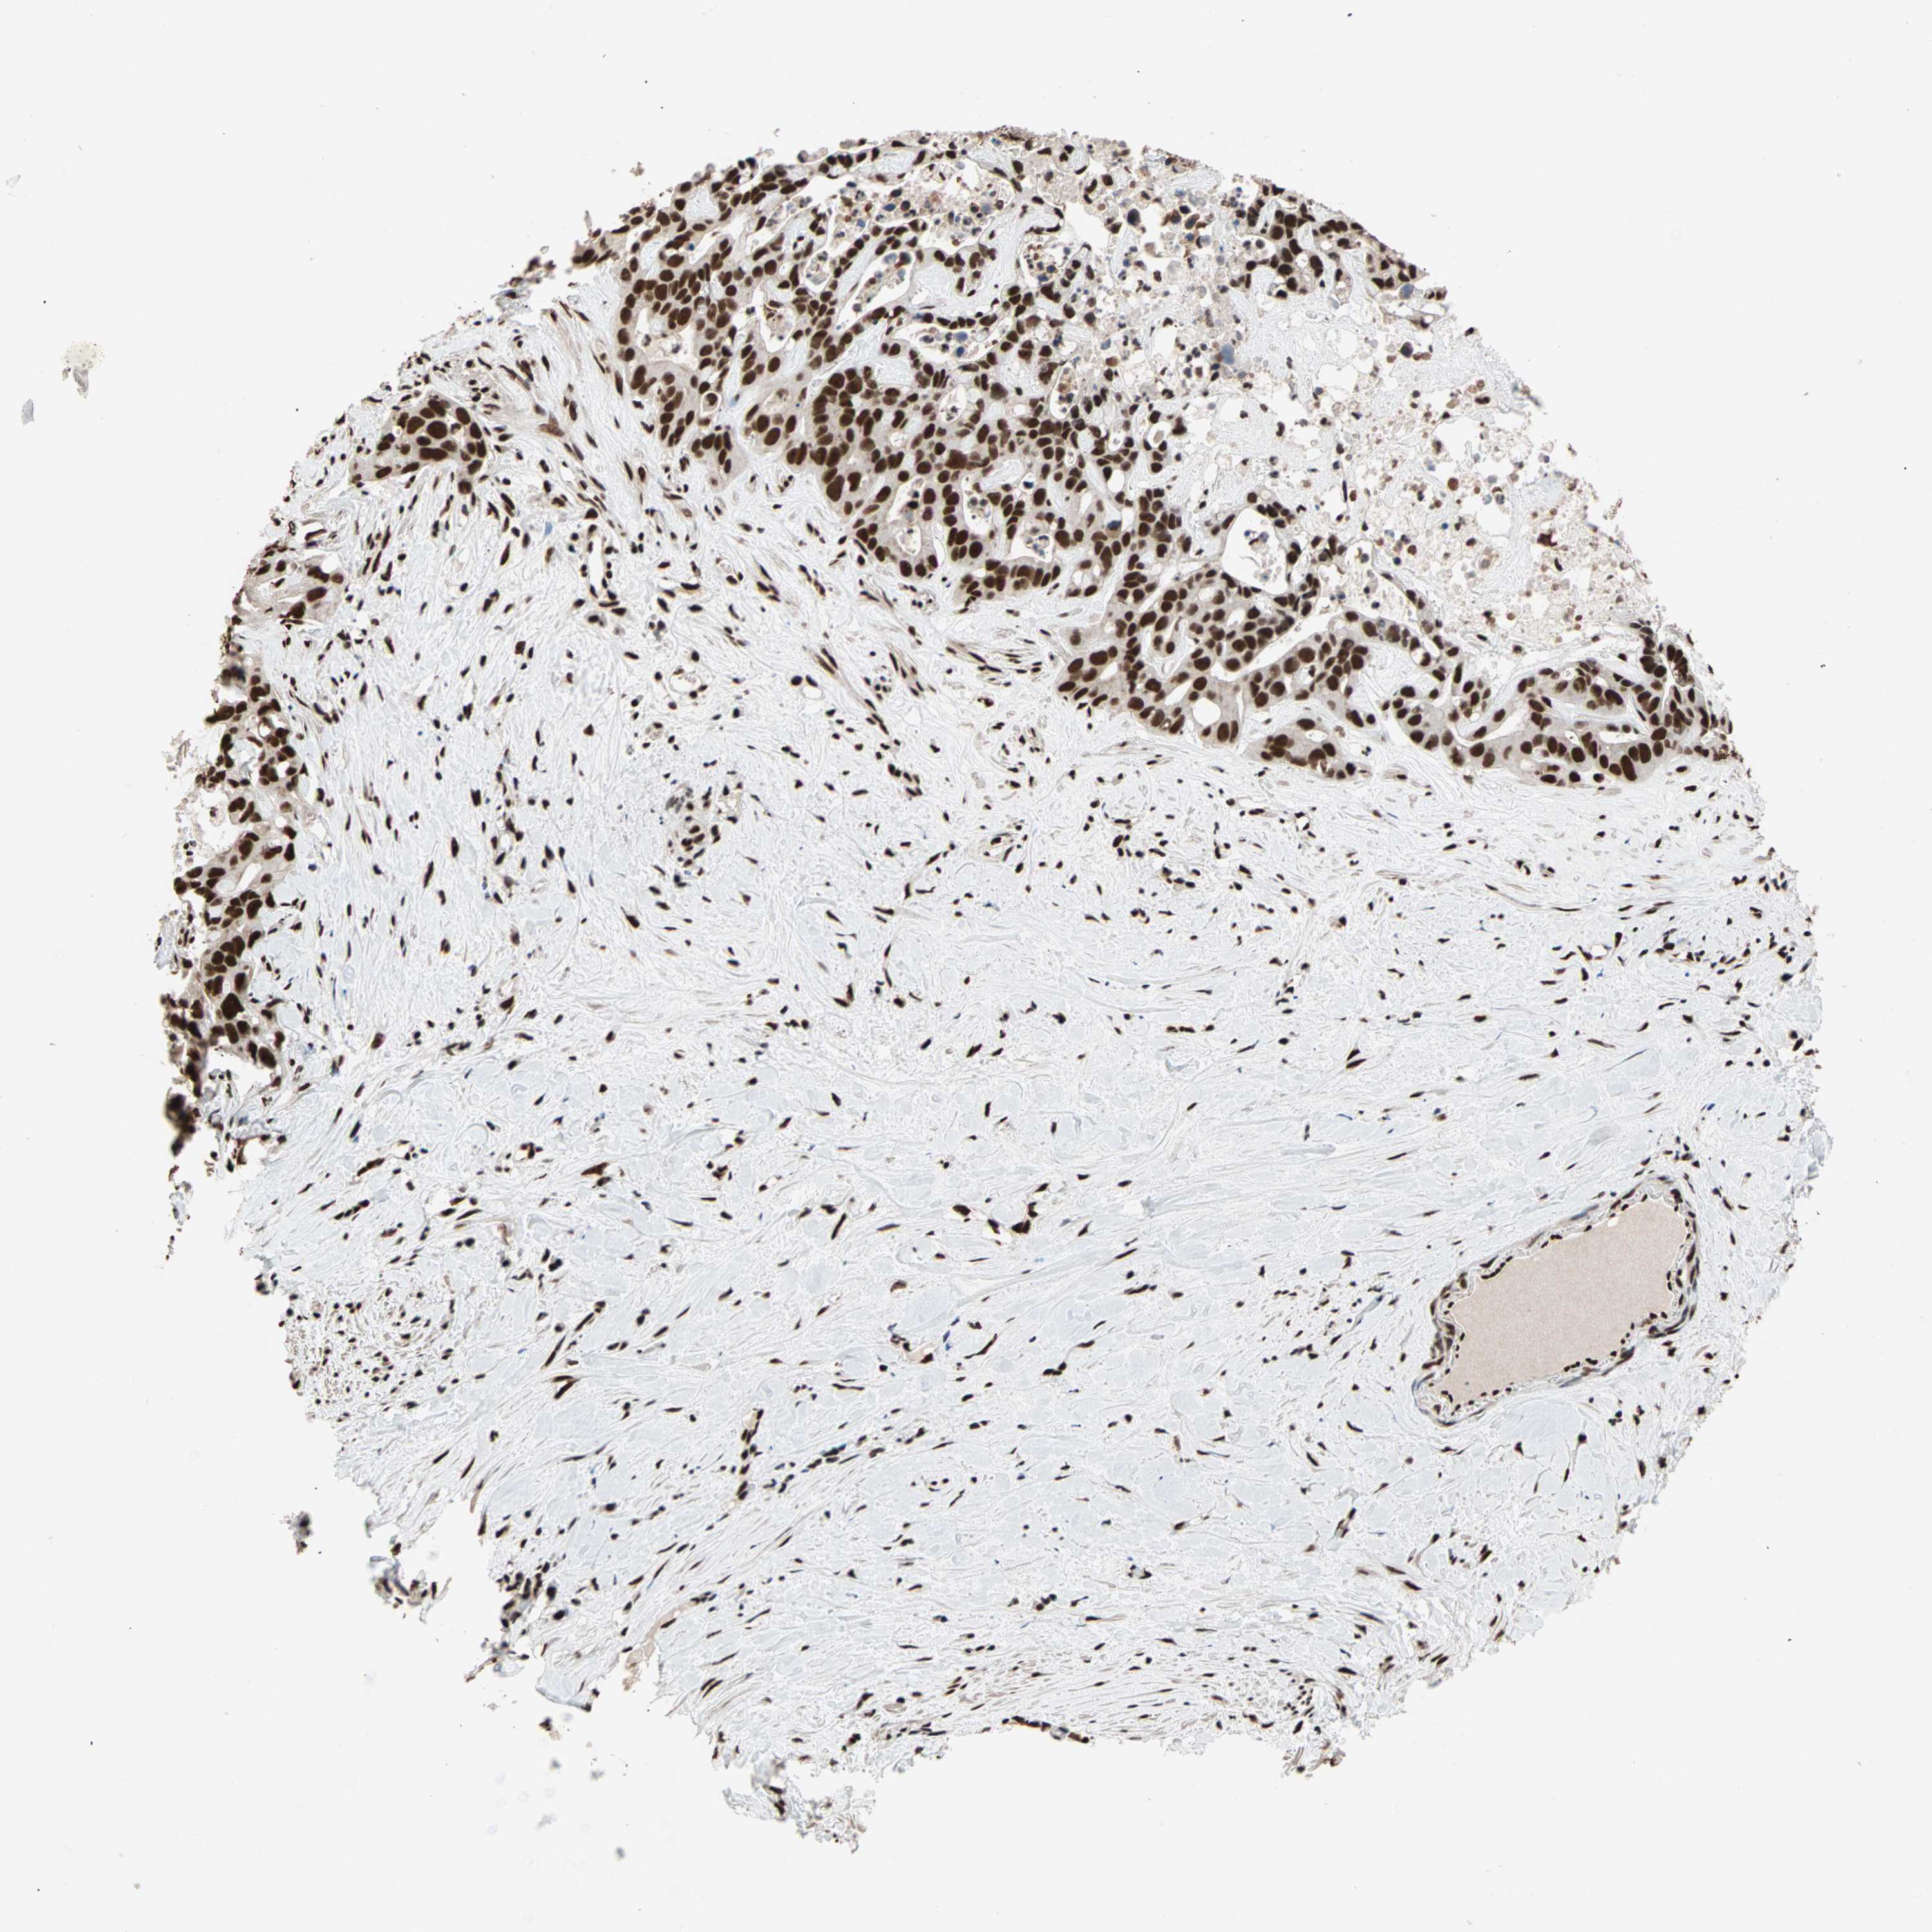

LIVER CANCER - Protein expressioni

A mouse-over function shows sample information and annotation data. Click on an image to view it in a full screen mode. Samples can be filtered based on level of antibody staining by selecting one or several of the following categories: high, medium, low and not detected. The assay and annotation is described here.

Note that samples used for immunohistochemistry by the Human Protein Atlas do not correspond to samples in the TCGA dataset.

Antibody stainingi

Antibody staining in the annotated cell types in the current human tissue is reported as not detected, low, medium, or high, based on conventional immunohistochemistry profiling in selected tissues. This score is based on the combination of the staining intensity and fraction of stained cells.

Each image is clickable and will lead to virtual microscopy that enables deeper exploration of all samples and also displays staining intensity scores, fraction scores and subcellular localization as well as patient and tissue information for each sample.

Antibody HPA007484

Staining

High

Medium

Low

Not detected

Intensity

Strong

Moderate

Weak

Negative

Quantity

>75%

75%-25%

<25%

None

Location

Nuclear

Cytoplasmic/membranous

Cytoplasmic/membranous,nuclear

Cholangiocarcinoma

Carcinoma, Hepatocellular, NOS